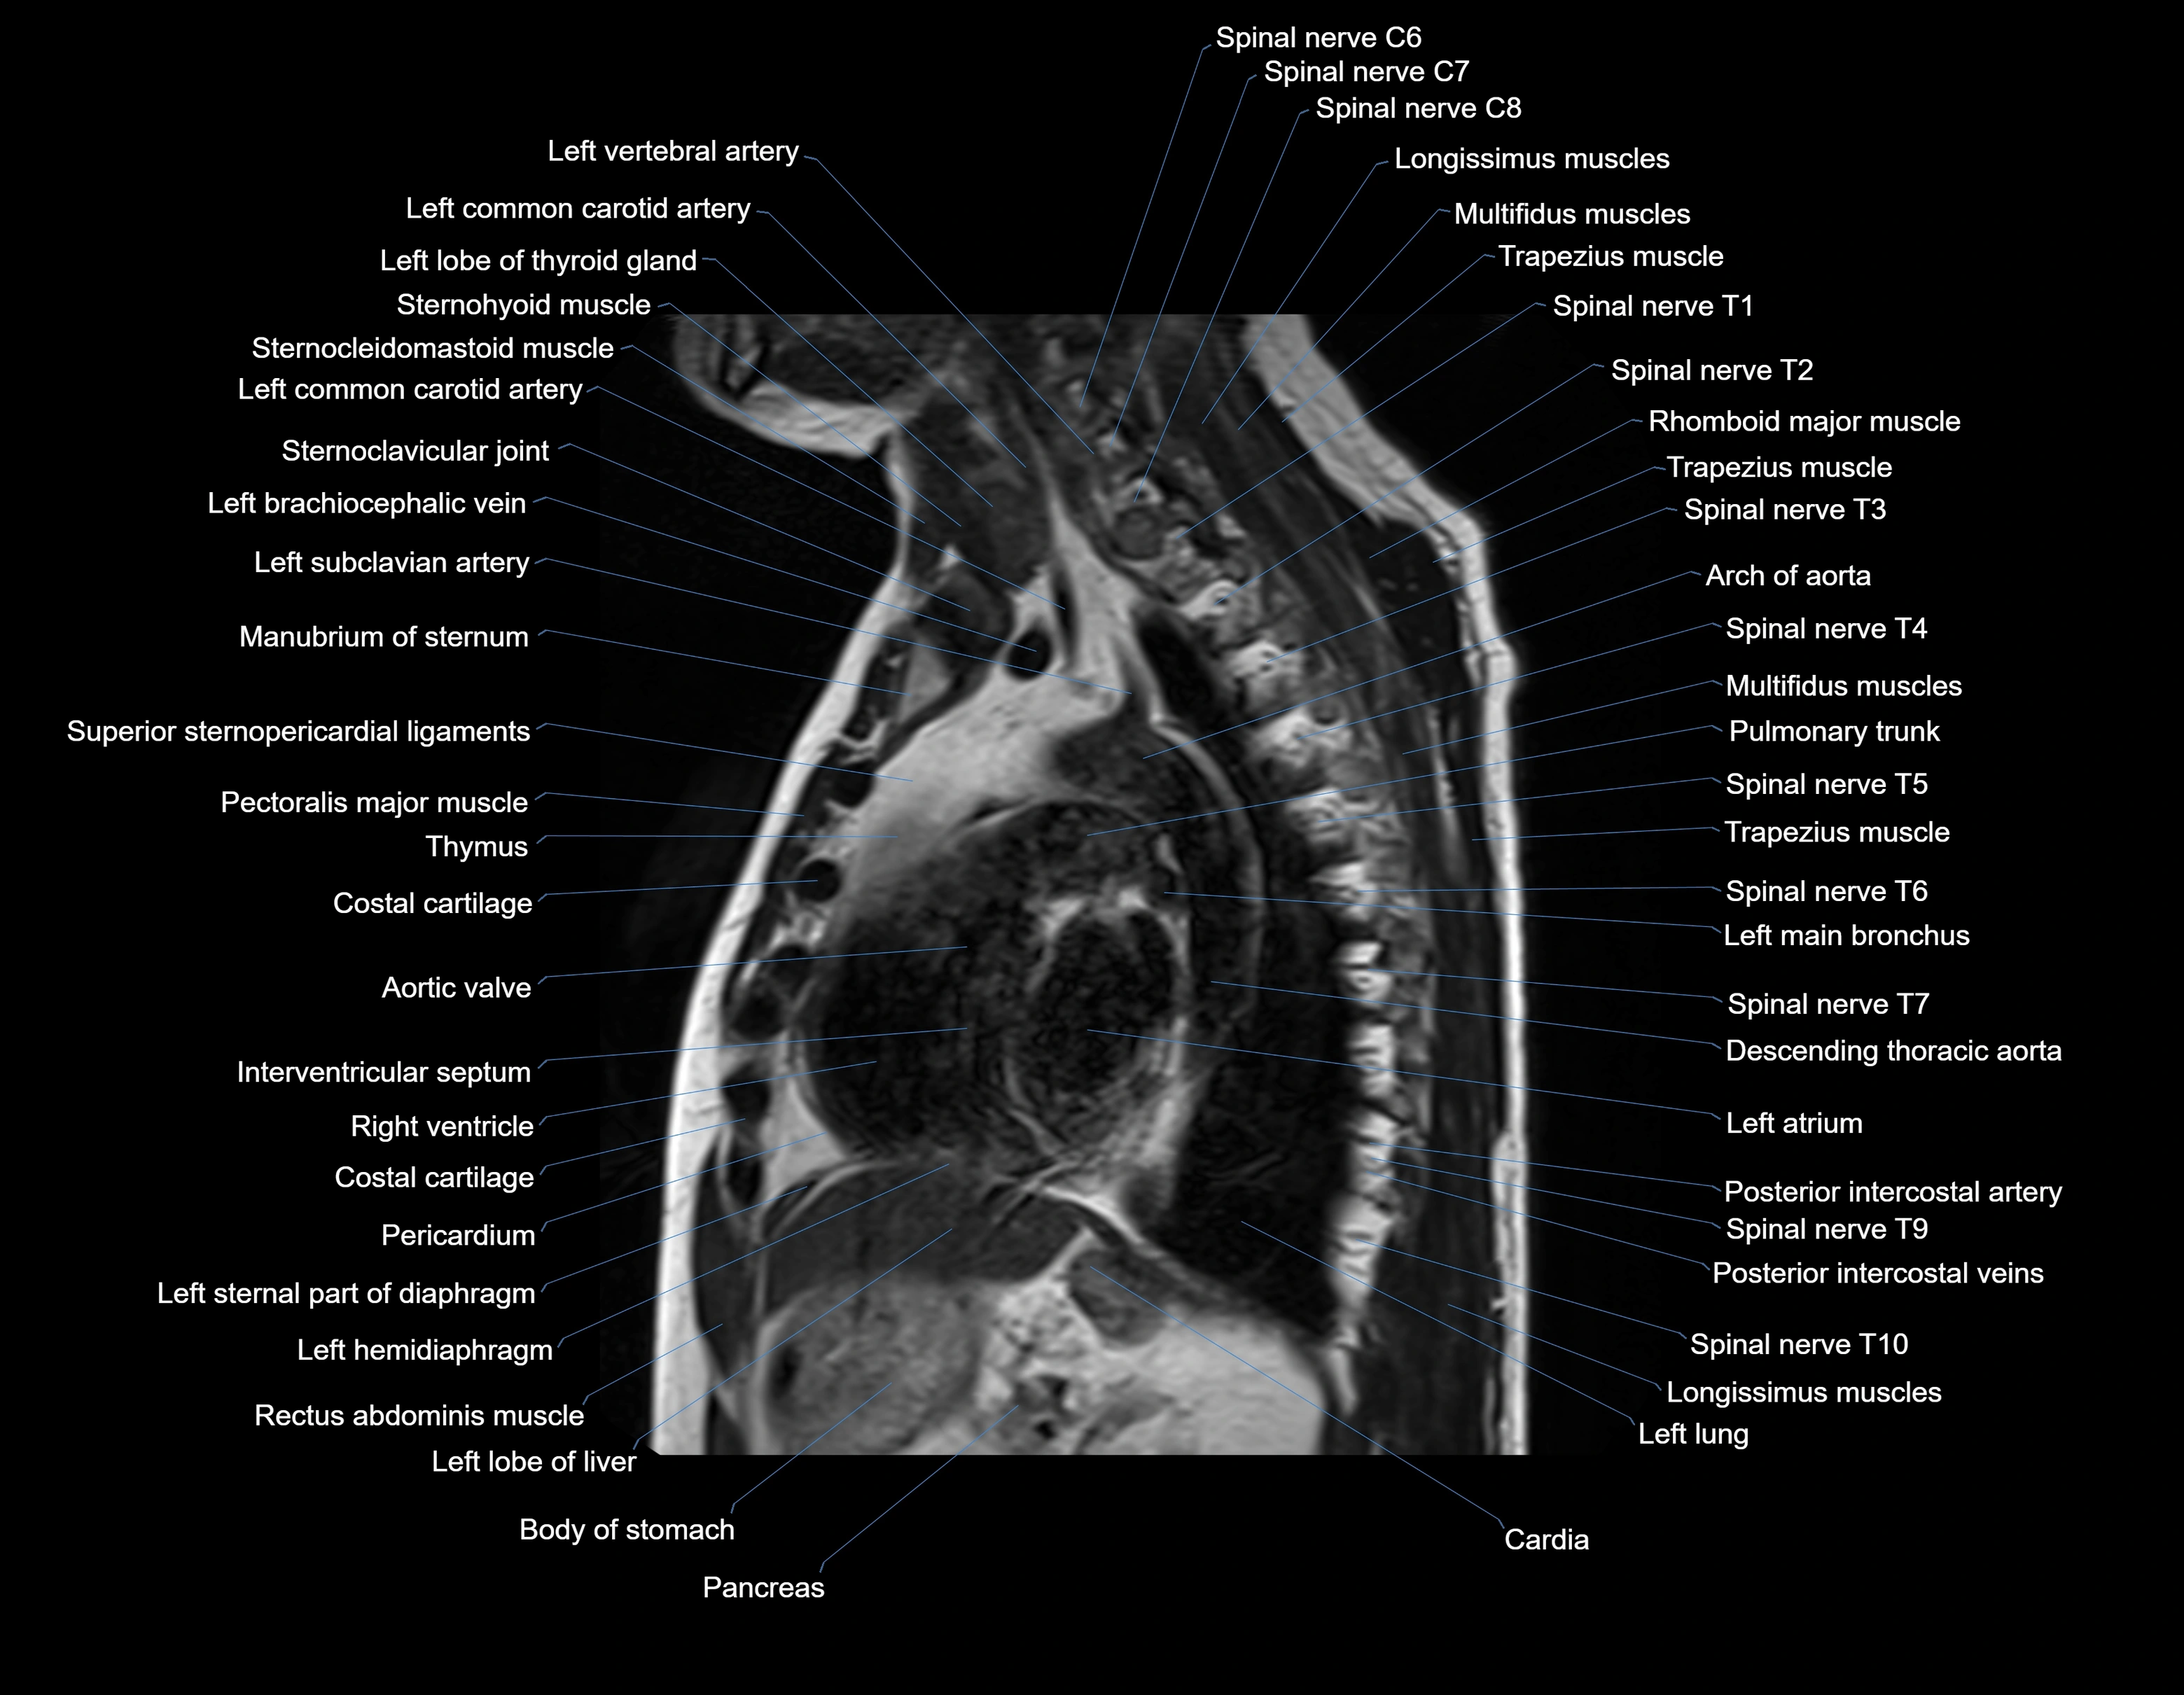

MRI images